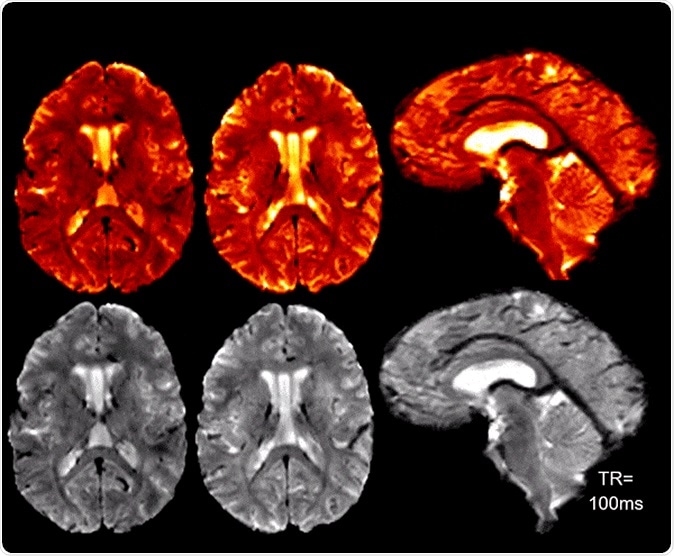

High SNR/CNR allows for real-time 7T MRI for brain pulsatility and CSF flow measurements. Credit: Radiofrequency (RF) Research Facility.

The team will help develop a new generation of imaging technology using the combination of these two imaging and antenna devices. Their focus is on achieving the highest ever resolution of the head and neck, with respect to both time and space. Ibrahim is already supervising the whole body 7T MRI device at Pitt’s Swanson School of Engineering, one of the most powerful in the world at human MRI imaging, and capable of allowing a very close look into structure and function of the human brain.